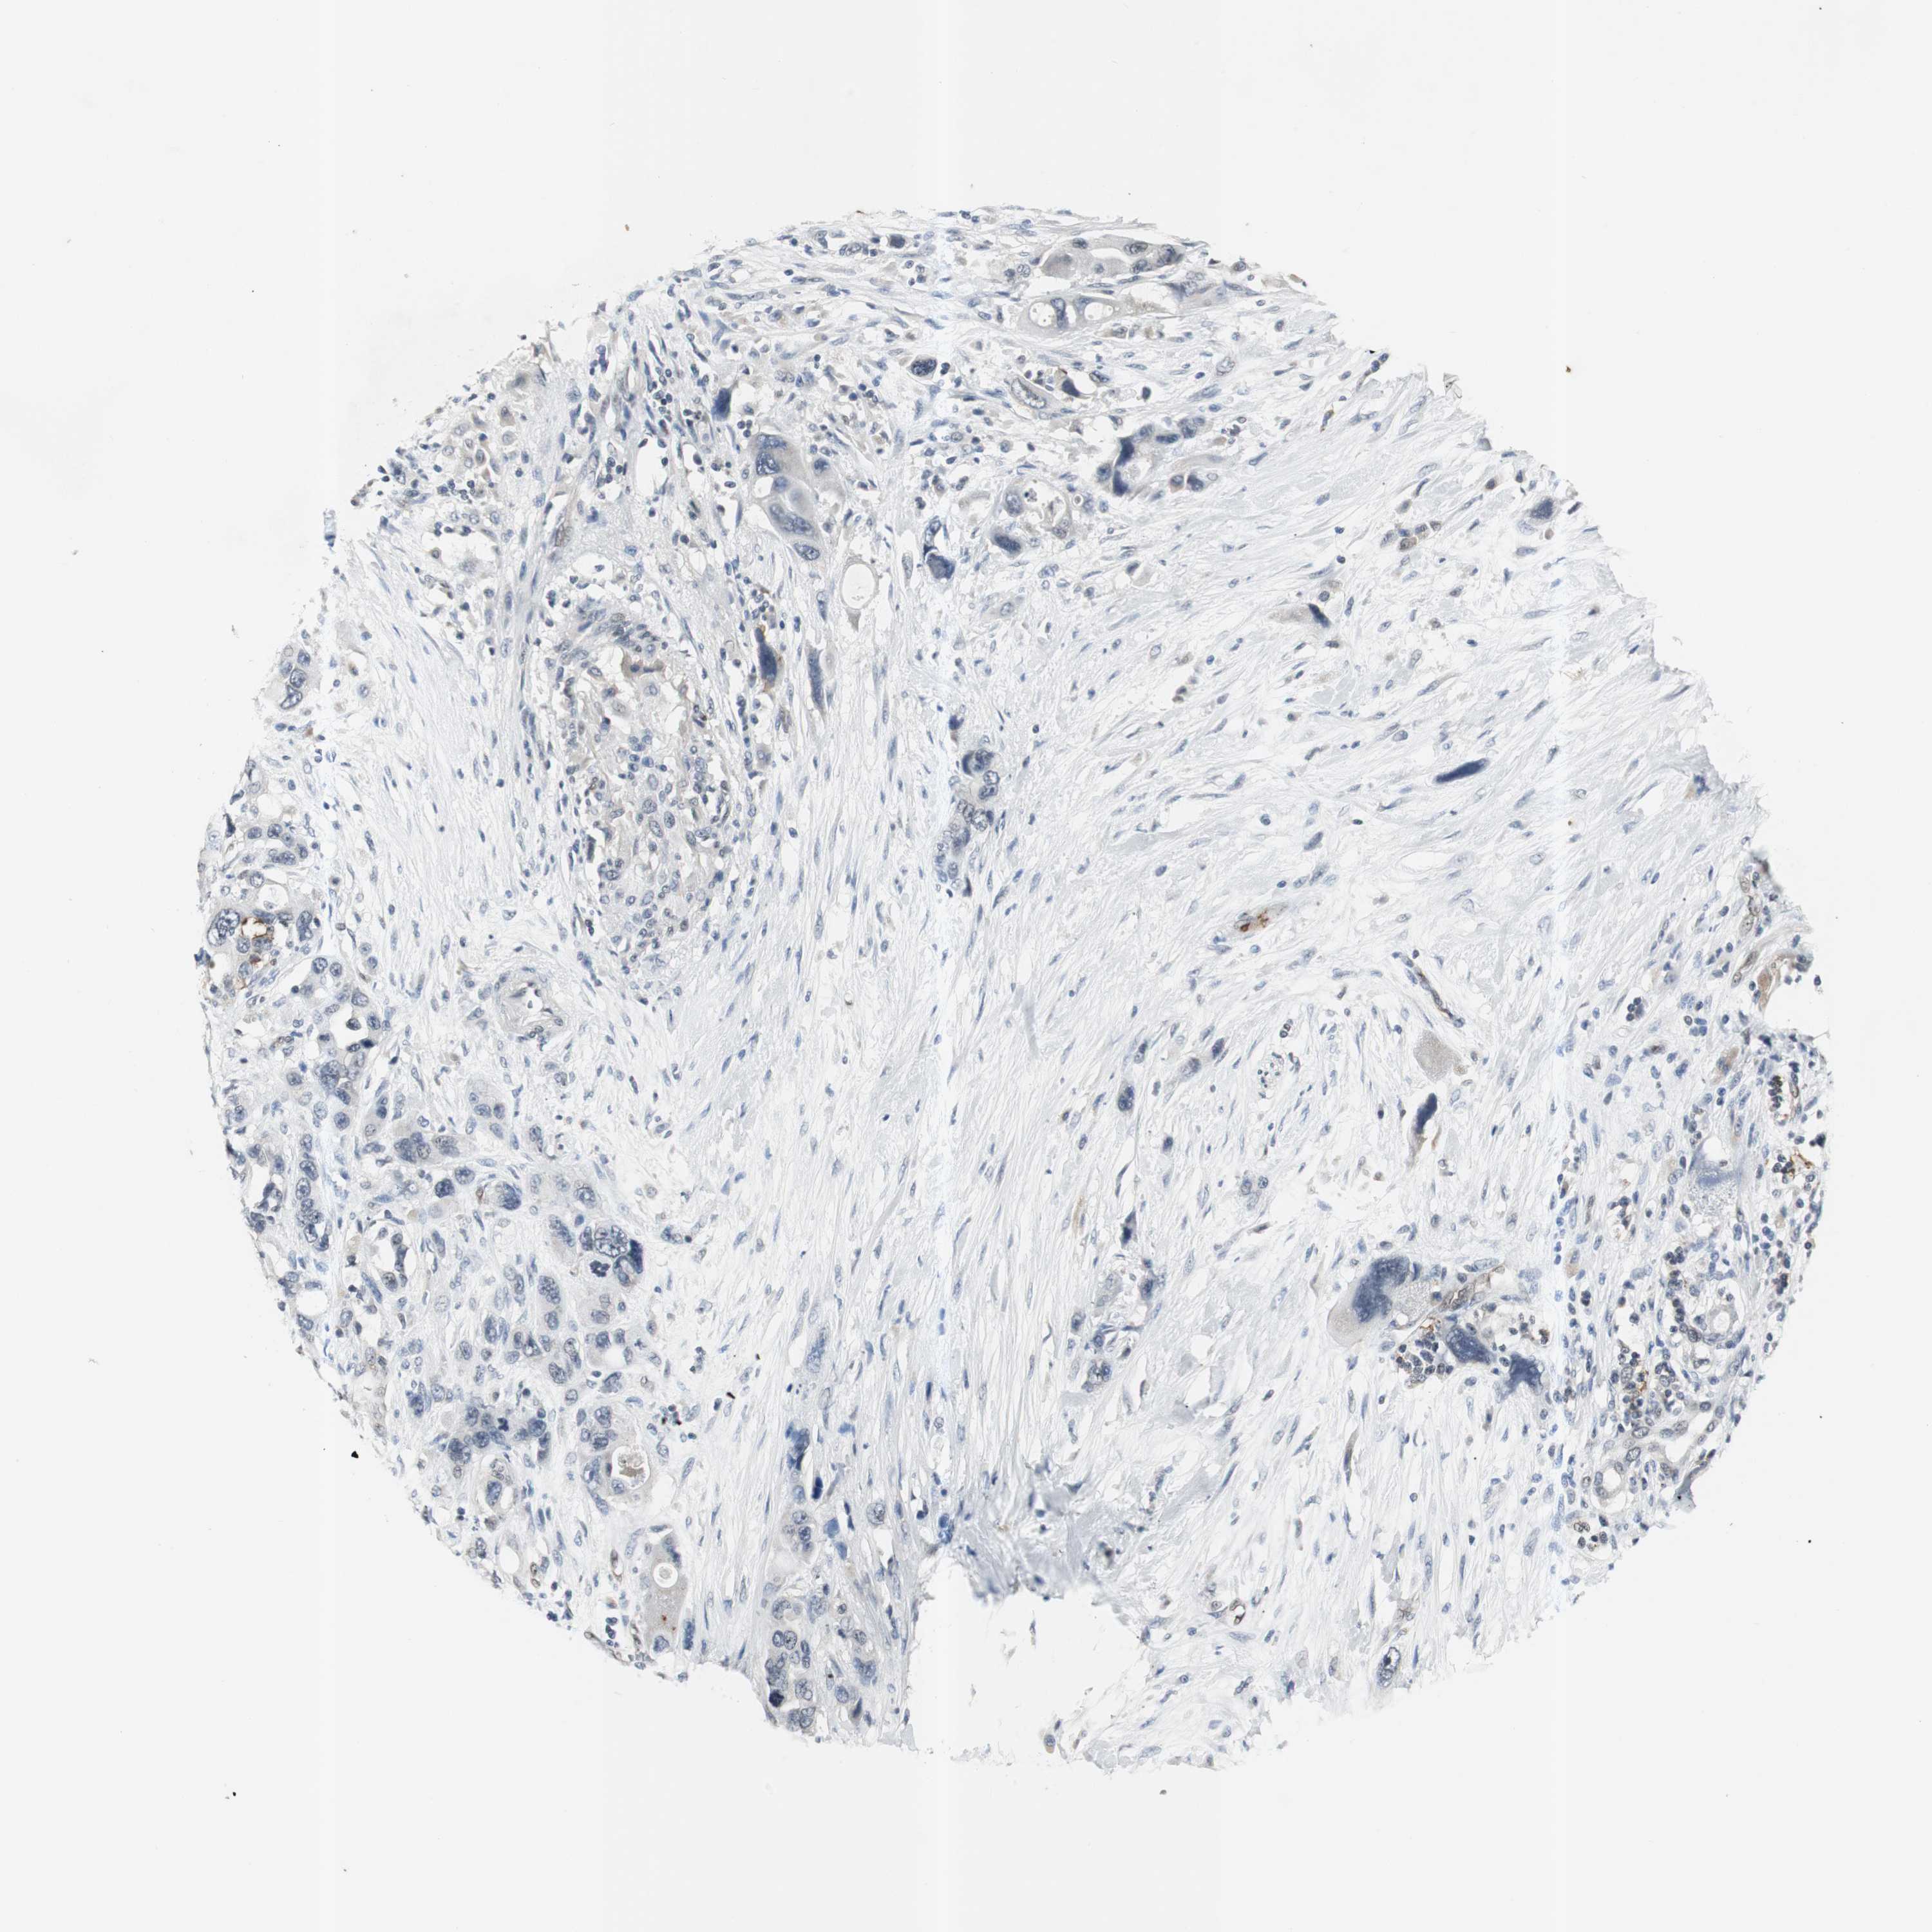

PANCREATIC CANCER - Protein expressioni

A mouse-over function shows sample information and annotation data. Click on an image to view it in a full screen mode. Samples can be filtered based on level of antibody staining by selecting one or several of the following categories: high, medium, low and not detected. The assay and annotation is described here.

Note that samples used for immunohistochemistry by the Human Protein Atlas do not correspond to samples in the TCGA dataset.

Antibody stainingi

Antibody staining in the annotated cell types in the current human tissue is reported as not detected, low, medium, or high, based on conventional immunohistochemistry profiling in selected tissues. This score is based on the combination of the staining intensity and fraction of stained cells.

Each image is clickable and will lead to virtual microscopy that enables deeper exploration of all samples and also displays staining intensity scores, fraction scores and subcellular localization as well as patient and tissue information for each sample.

Antibody CAB005389

Staining

High

Medium

Low

Not detected

Intensity

Strong

Moderate

Weak

Negative

Quantity

>75%

75%-25%

<25%

None

Location

Nuclear

Cytoplasmic/membranous

Cytoplasmic/membranous,nuclear

Adenocarcinoma, NOS

Adenocarcinoma, metastatic, NOS